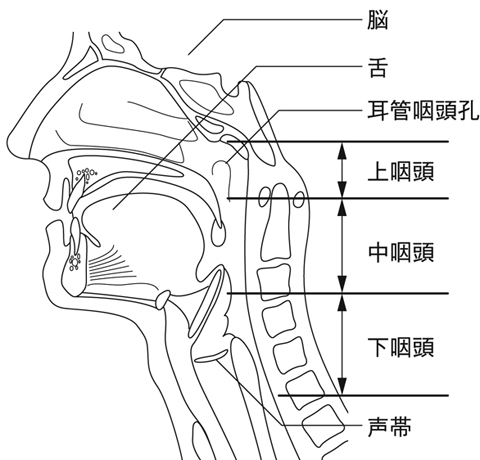

咽頭がんを早期発見するには そもそも咽頭とはどこのこと Helc